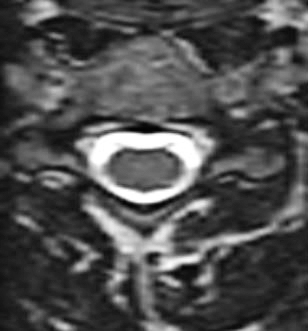

Axial T2-viktad MR-bild mellan C4 och C5 på en 68-årig kvinna med balanssvårigheter, klumpighet och radikulopati mot händerna. I status fanns bilateralt positivt Hoffmanns tecken och stegrade reflexer. I bilden ses en bredbasig diskbuktning och fasettledshypertrofi som försnävar spinalkanalen.